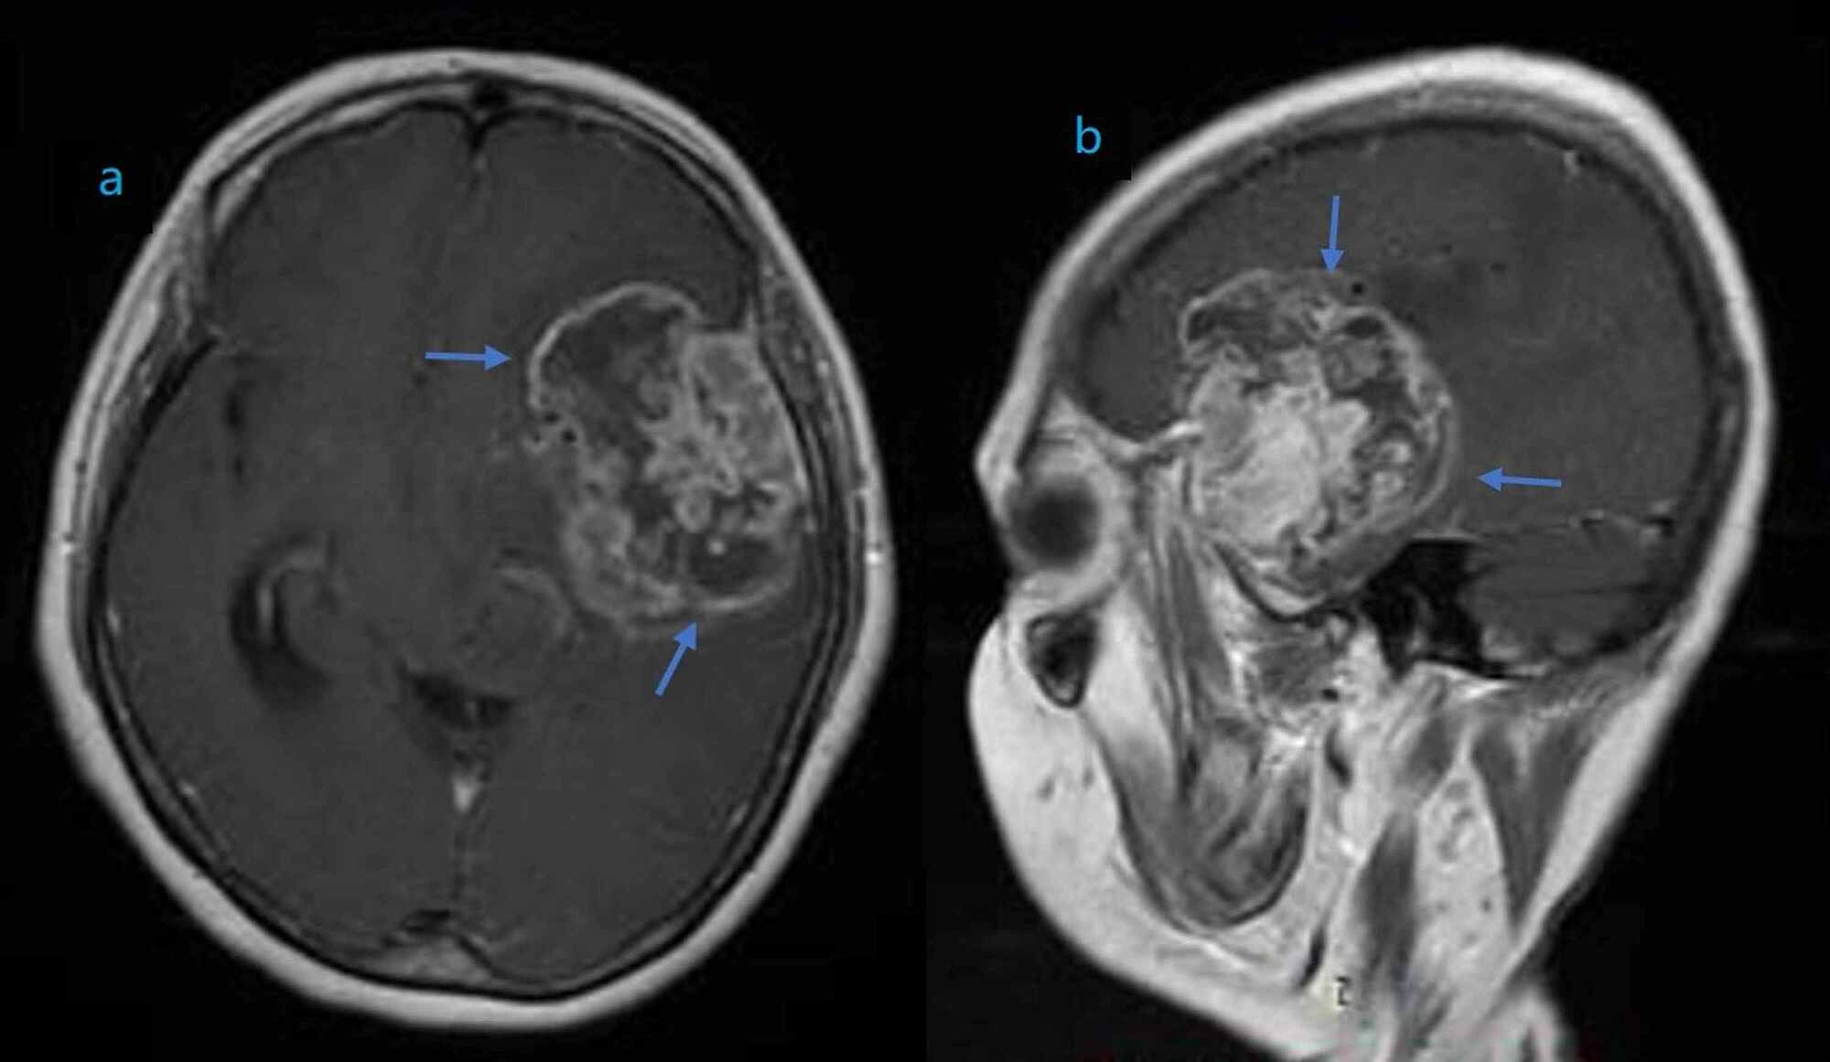

صورة 1: يُظهر هذا التصوير بالرنين المغناطيسي وجود ورم دبقي عالي الدرجة في الفص الصدغي والجبهي الأيسر.